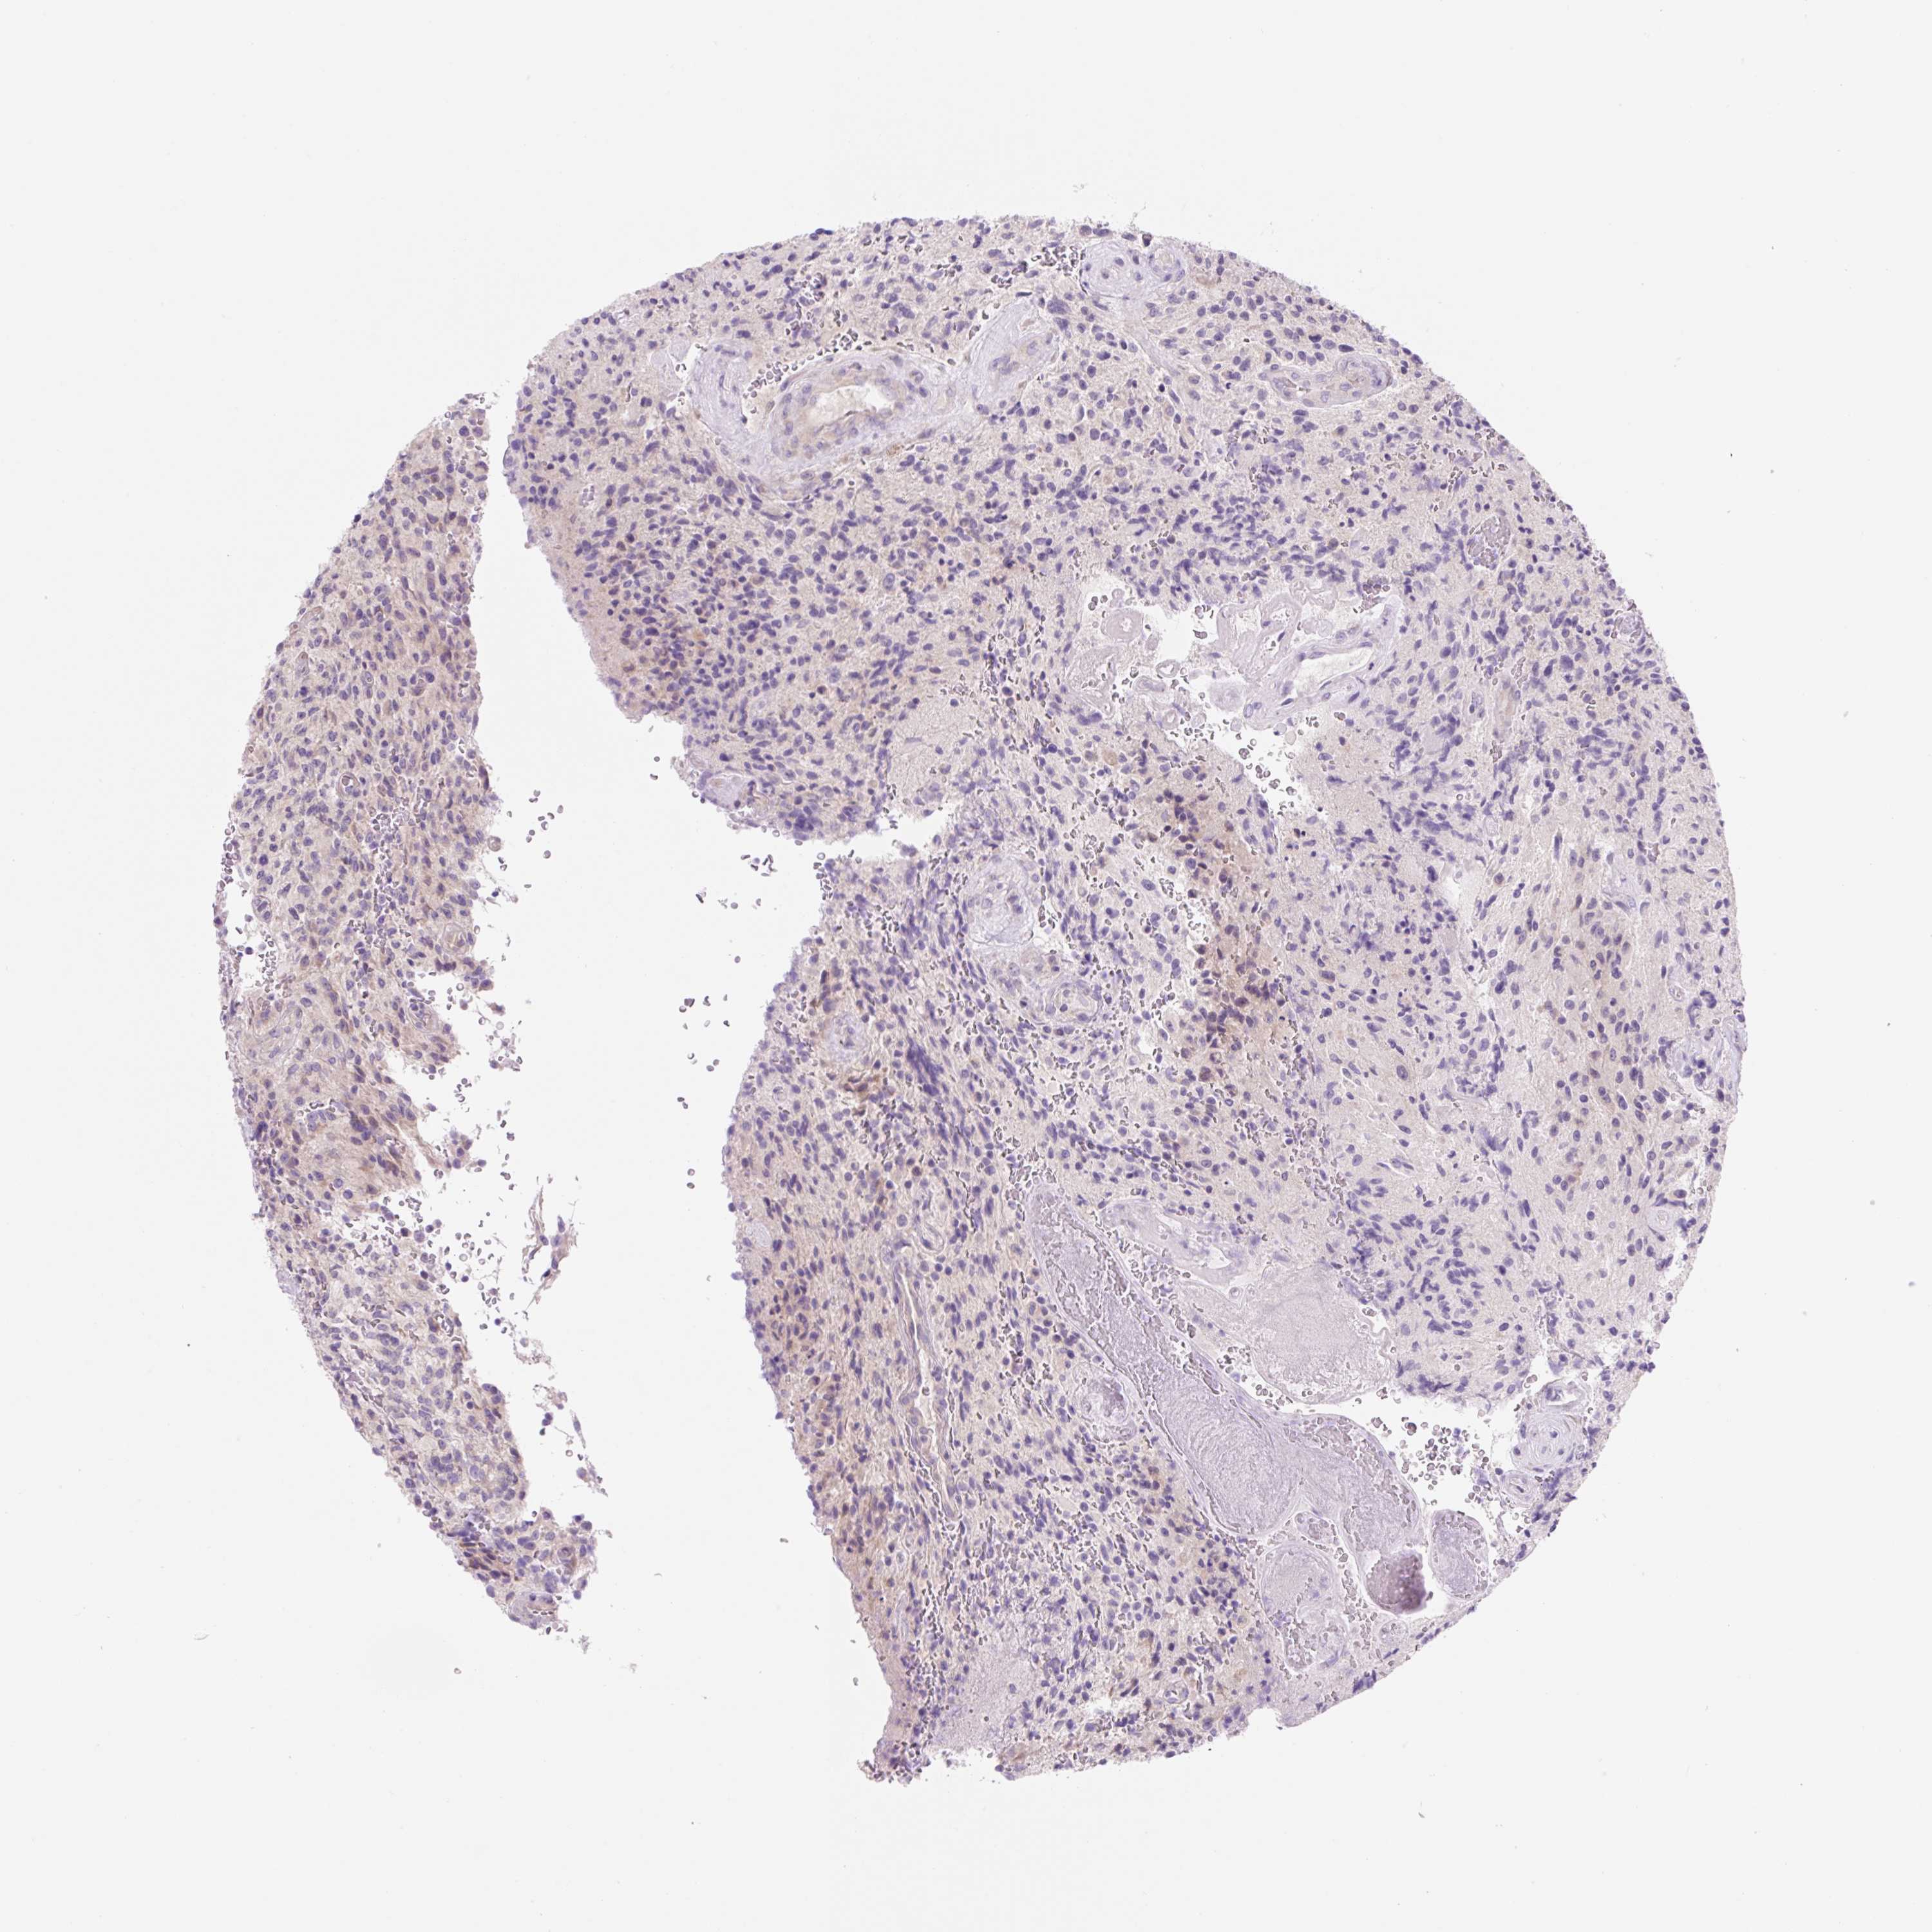

GLIOMA - Protein expressioni

A mouse-over function shows sample information and annotation data. Click on an image to view it in a full screen mode. Samples can be filtered based on level of antibody staining by selecting one or several of the following categories: high, medium, low and not detected. The assay and annotation is described here.

Note that samples used for immunohistochemistry by the Human Protein Atlas do not correspond to samples in the TCGA dataset.

Antibody stainingi

Antibody staining in the annotated cell types in the current human tissue is reported as not detected, low, medium, or high, based on conventional immunohistochemistry profiling in selected tissues. This score is based on the combination of the staining intensity and fraction of stained cells.

Each image is clickable and will lead to virtual microscopy that enables deeper exploration of all samples and also displays staining intensity scores, fraction scores and subcellular localization as well as patient and tissue information for each sample.

Antibody HPA046985

Antibody HPA053526

Staining

High

Medium

Low

Not detected

Intensity

Strong

Moderate

Weak

Negative

Quantity

>75%

75%-25%

<25%

None

Location

Nuclear

Cytoplasmic/membranous

Cytoplasmic/membranous,nuclear

Glioma, malignant, High grade

Glioma, malignant, Low grade